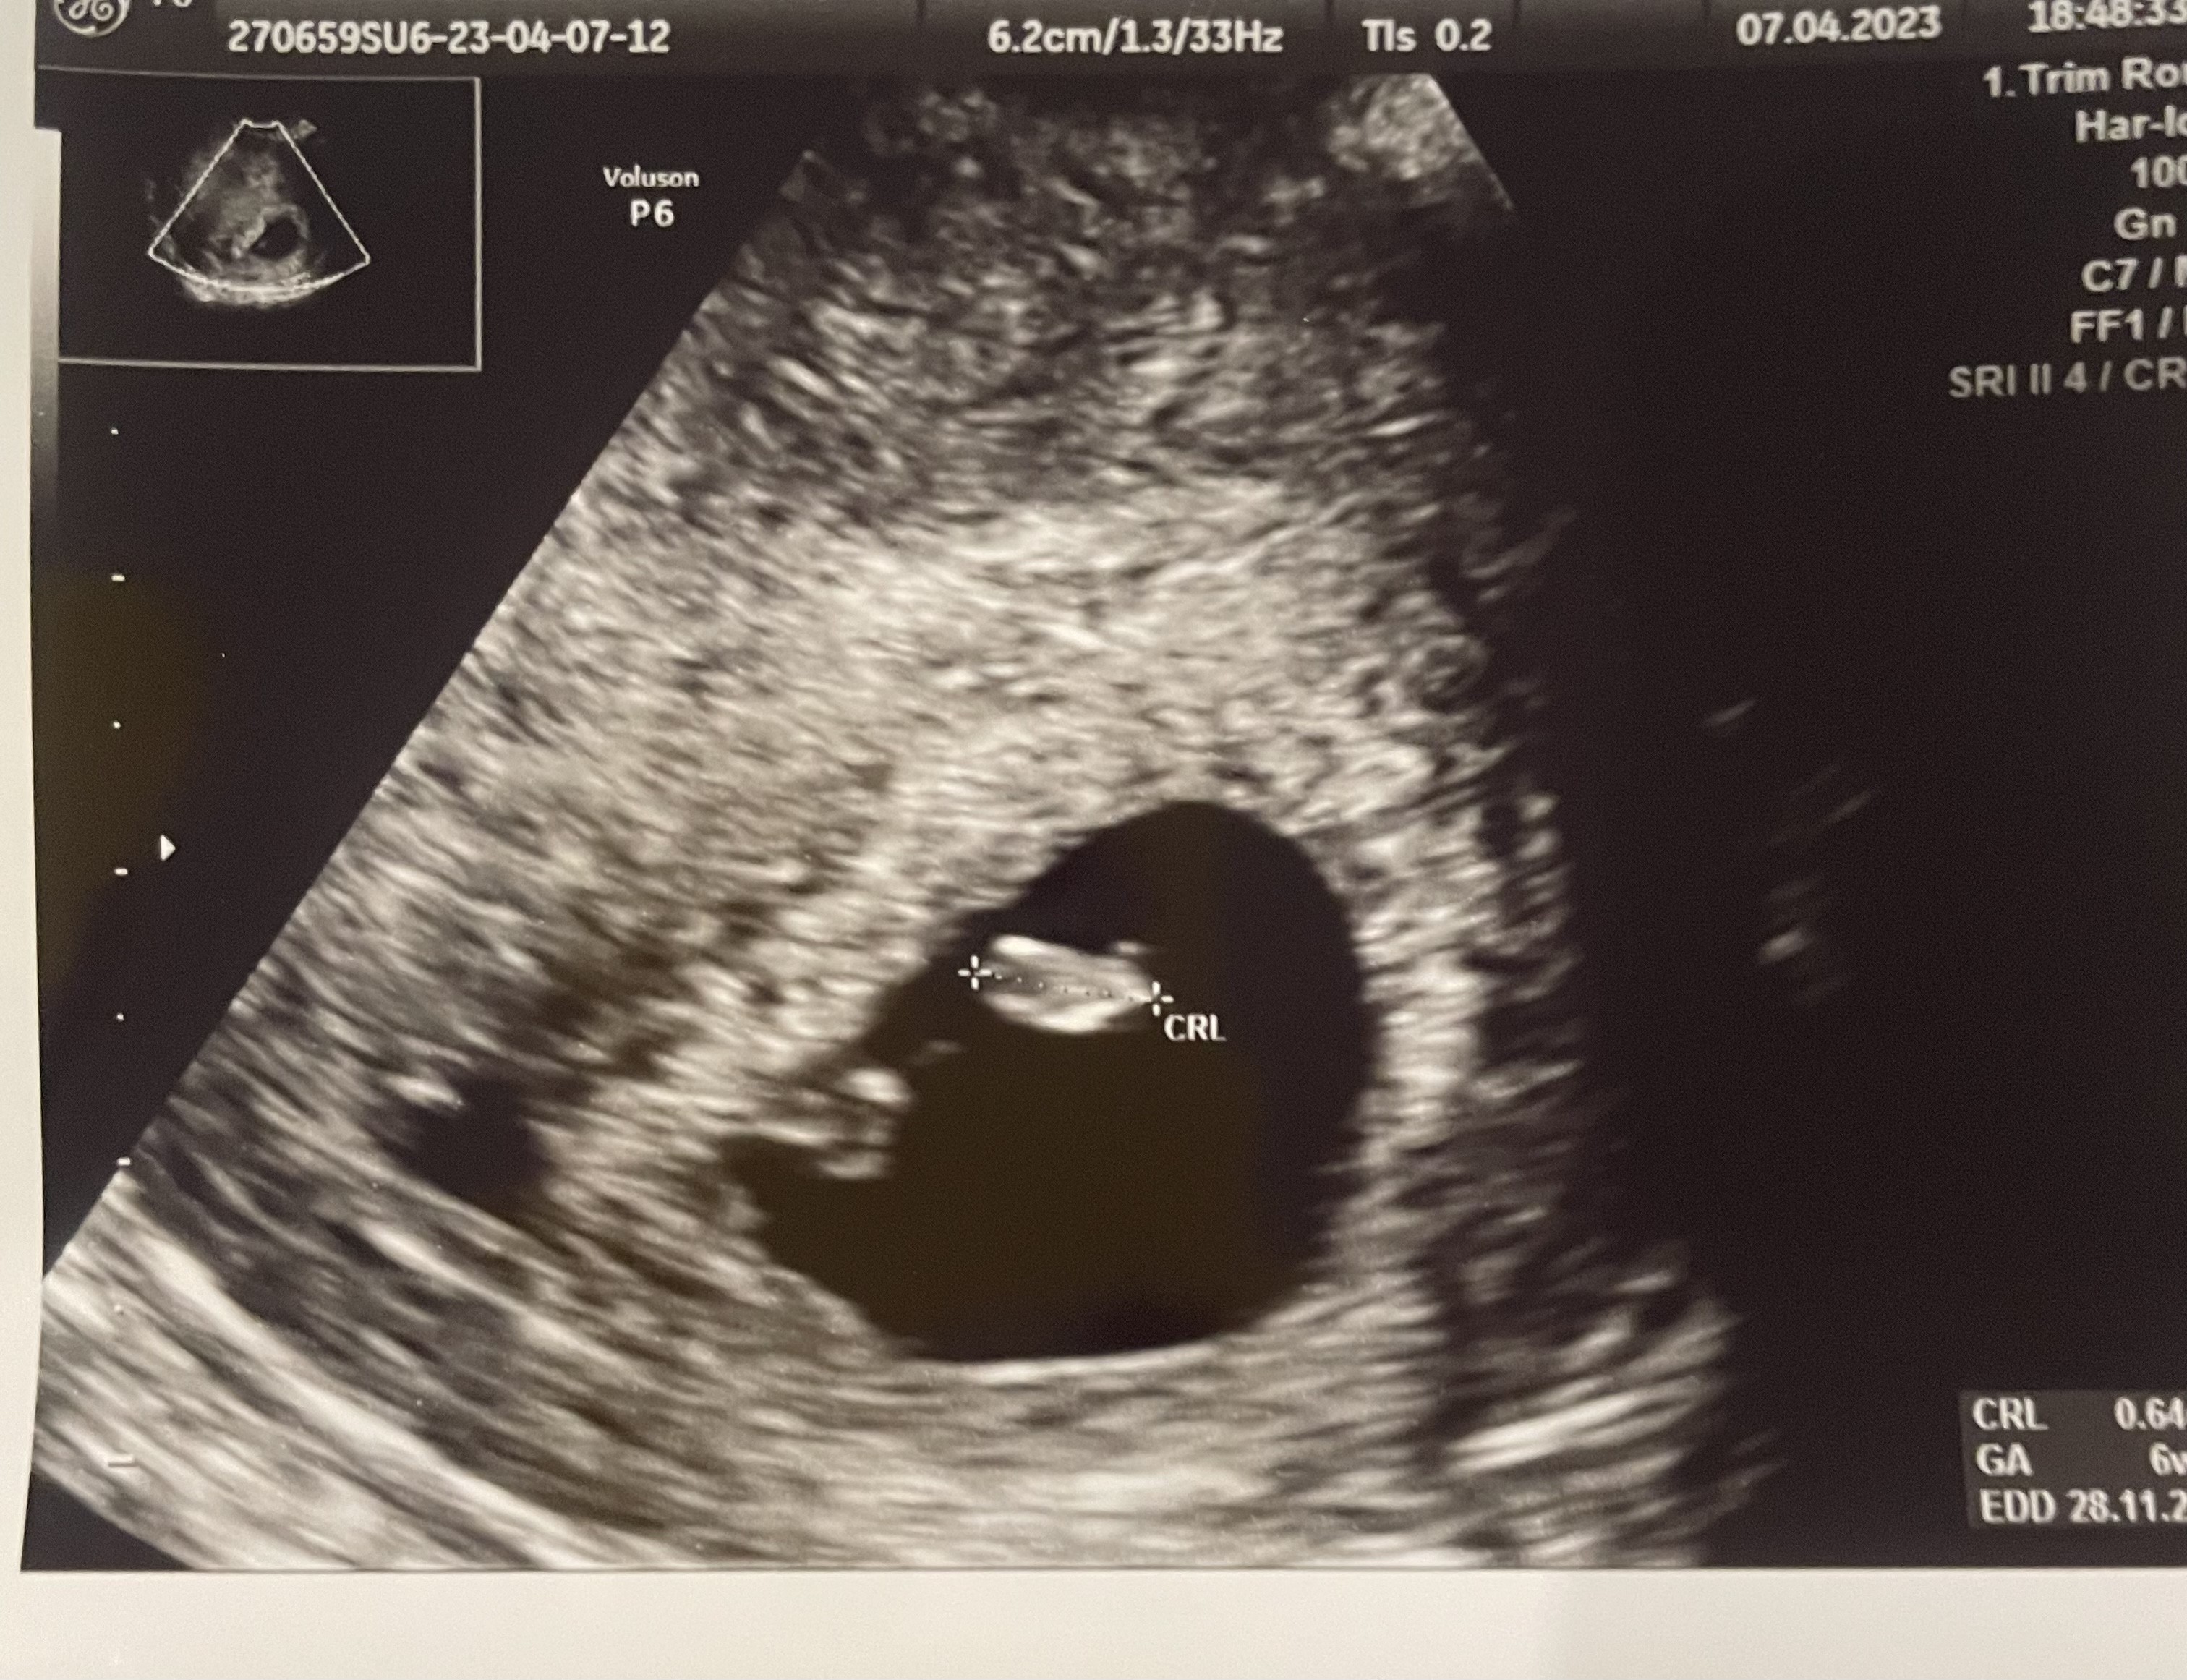

Tak po wizycie ❤️ dzidzia jest, serduszko bije! Jedyne co to mam małe krwiaczki w okolicy i mogę z nich krwawić, No ale jak do tej pory to miałam tylko plamienie kawa z mlekiem w terminie okresu. Umówiłam się z ginem ze gdyby coś się działo to wystawi mi receptę na dupka. Termin z om mam na 25.11 a z usg 28.11 ale synek tez był trochę młodszy i wiem ze owu miałam raczej dwa dni później:)

Załączniki

• 88F0C741-CDEB-40DC-8022-71356BE4564B.jpeg

88F0C741-CDEB-40DC-8022-71356BE4564B.jpeg

1,3 MB · Wyświetleń: 124